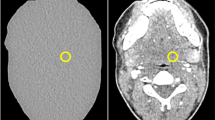

Seven anatomically identical phantoms mimicking a patient’s neck were created based on previously published methods [15]. Briefly, the phantoms were produced from seven different versions of a CT image of a patient’s neck: the original, unmodified CT image and six versions of the same image, where lesions of 1 cm diameter were inserted through pixelwise subtraction of 30 HU in a circular region of interest in different locations throughout the parapharyngeal space. Radiopaque 3D printing with potassium-iodide-doped ink and paper-based 3D printing were used to produce the phantoms with 1 cm thickness [16, 17]. The method of phantom creation was the same as described in more detail previously [15], except that all lesions had 30 HU contrast and were distributed throughout the parapharyngeal space. This lesion contrast was selected to create lesions at the interface between detectable and undetectable based on that previous study. Six phantoms thus contained one low-contrast lesion of 1 cm diameter and 30 HU contrast in different locations of the parapharyngeal space. One phantom did not contain any lesion. Figure 1 shows illustrations and CT images of the phantoms. For image acquisition, the 1-cm-thick phantoms were inserted into a full-size head and neck phantom as shown in suppl. fig. 1.

Drawings and CT images of the phantoms used for protocol assessment. Lesions are drawn in gray and indicated by white arrows in the CT images. The CT images shown here were acquired with 120-kVp tube voltage, TCM SD of 7.5, and a pitch of 0.813 and reconstructed with AIDR 3D (corresponding to the reference protocol used in this study). All images are displayed with window level 40 and window width 350